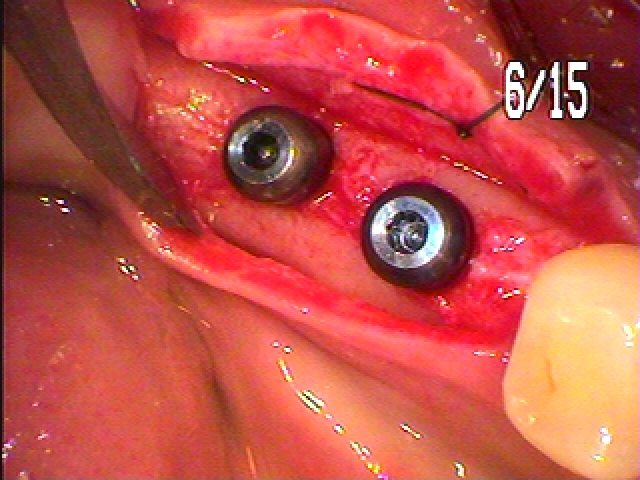

カフを取り付けています